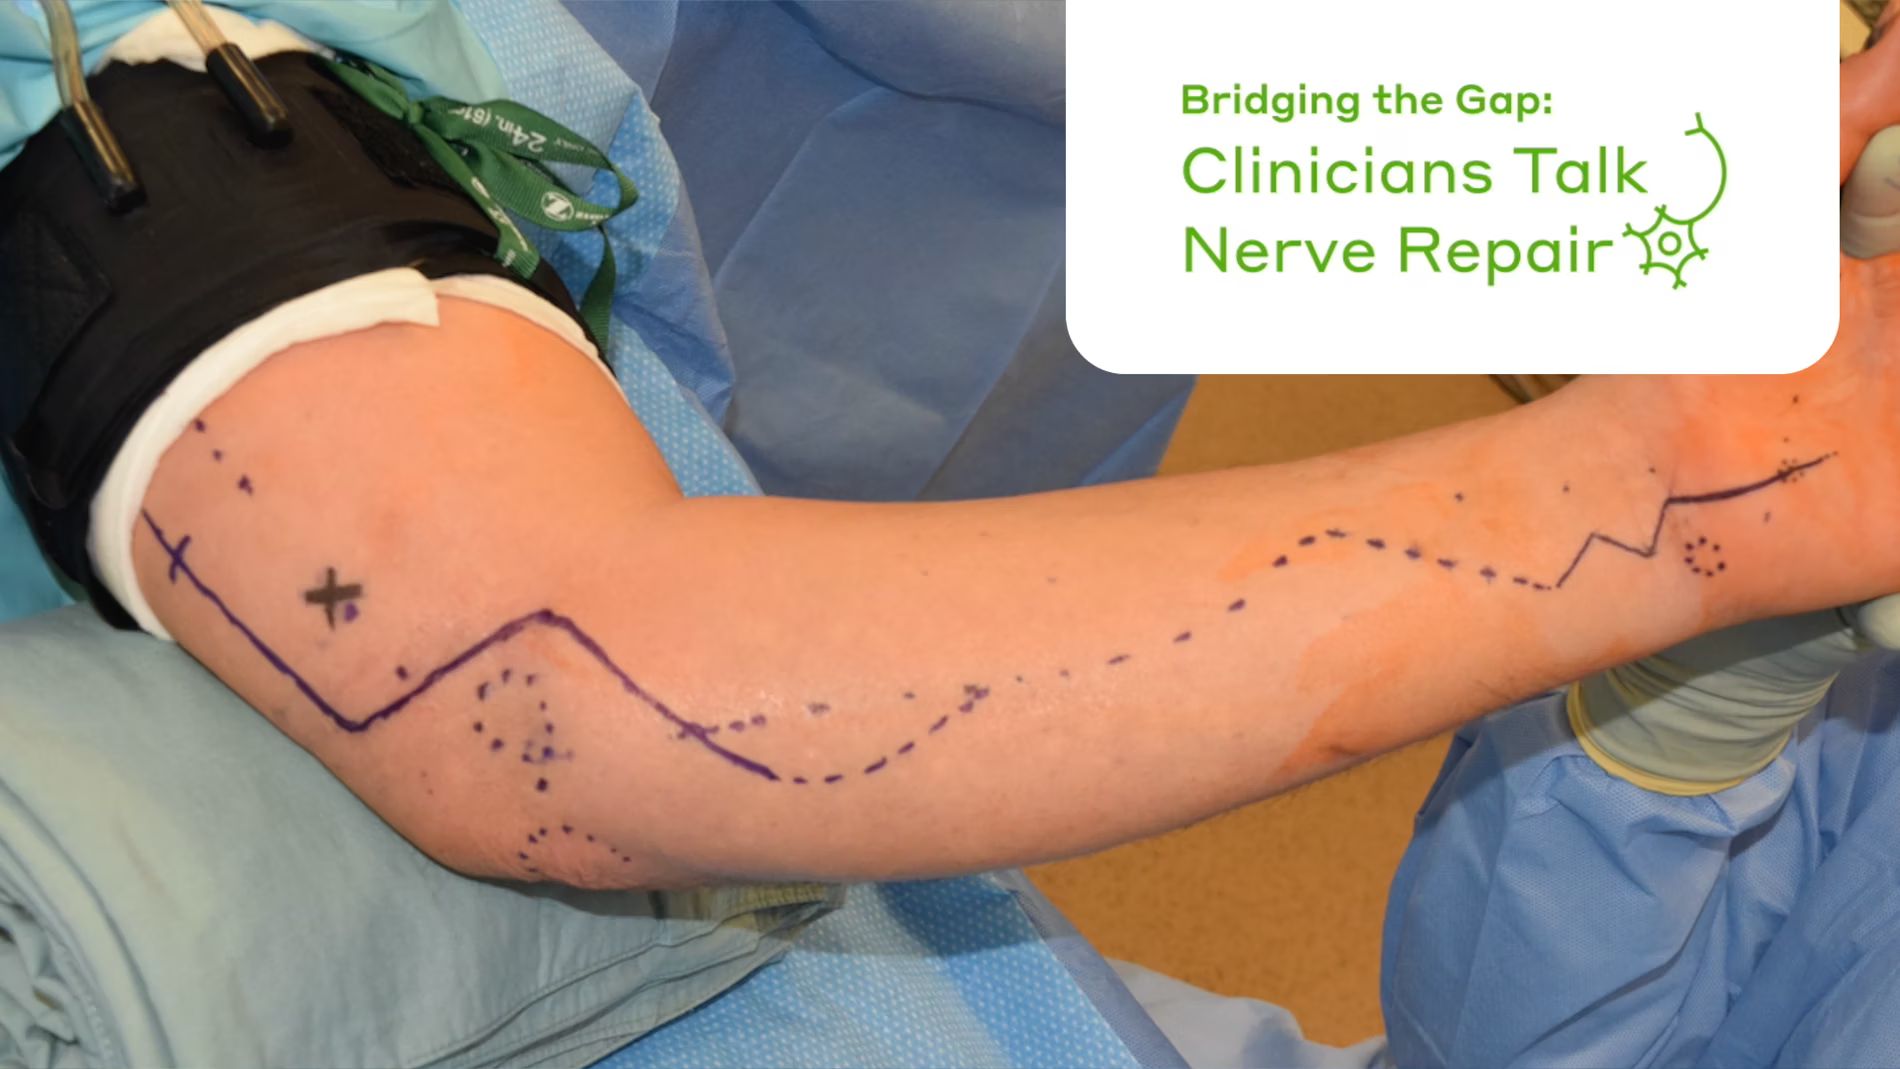

Targeted Muscle Reinnervation (TMR)

A modern surgical technique for treating transected nerve endings.

By Sunishka Wimalawansa, MD & Ian Valerio, MD